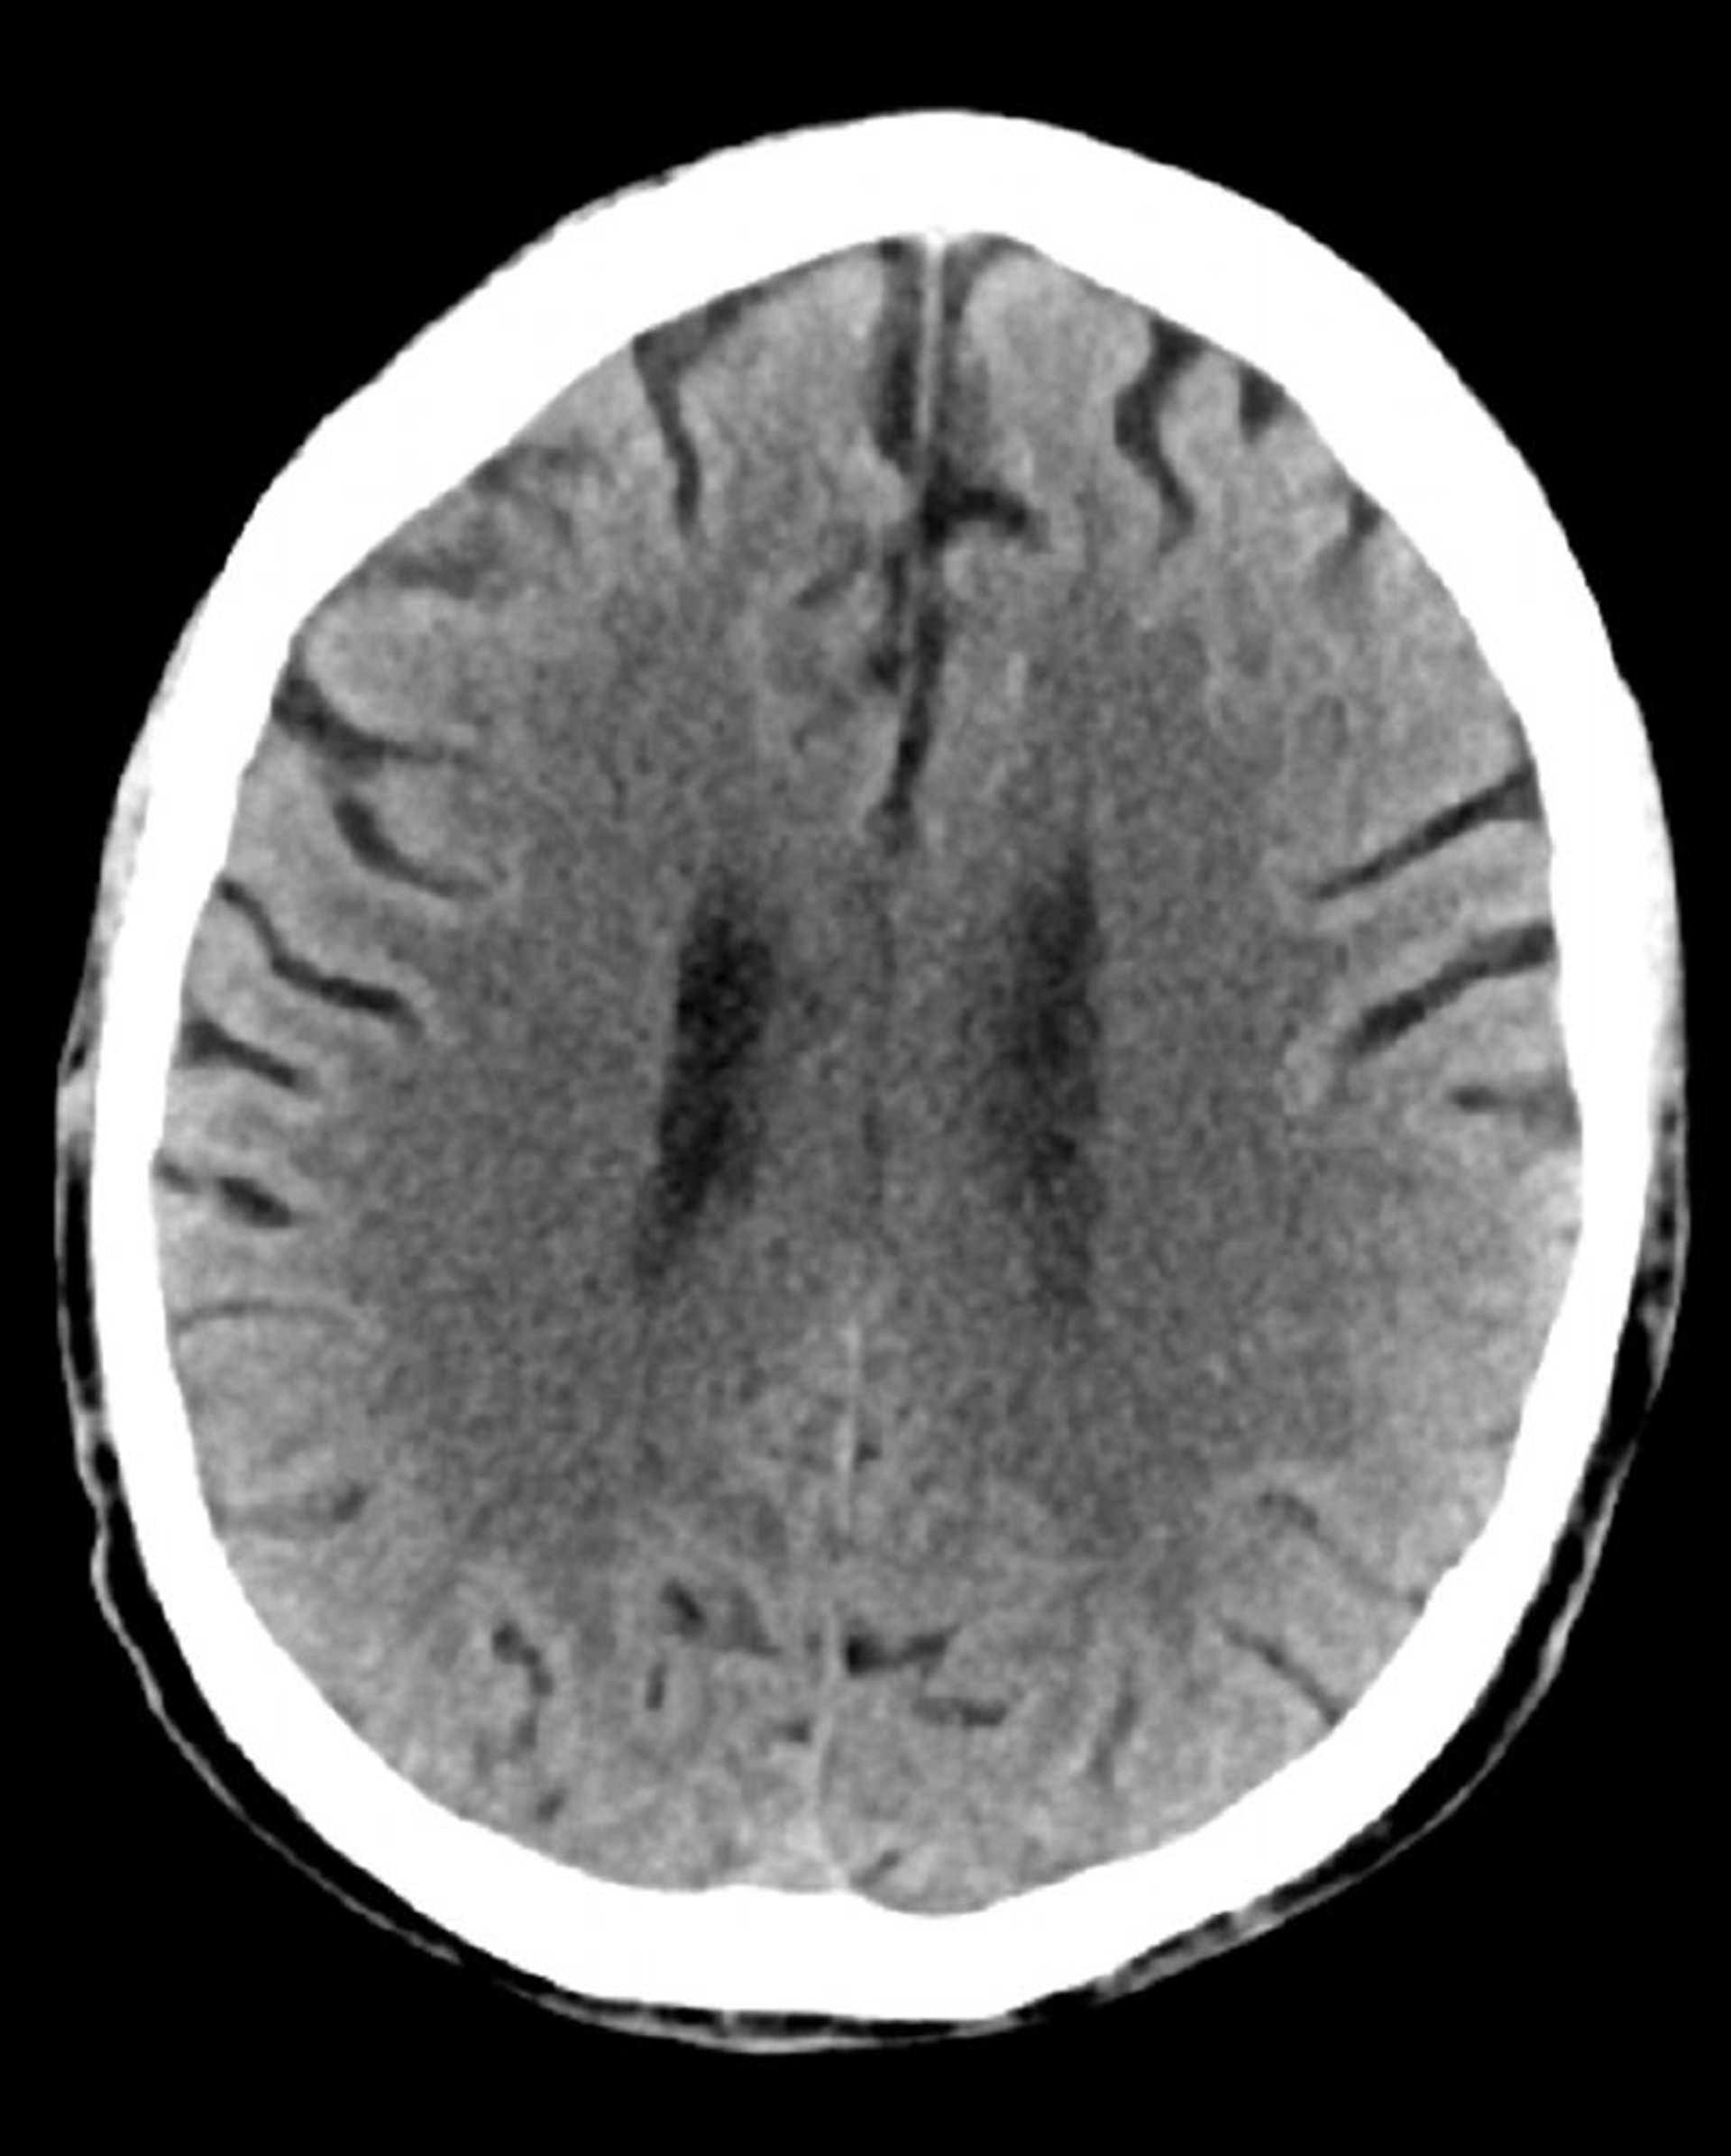

Стандартное КТ-сканирование головы (взрослые, возраст 74 года) – слайд 3

Это изображение –обычная компьютерная томография головы взрослого человека в возрасте 74 лет. По сравнению со стандартной компьютерной томографией головы пациента 30-летнего возраста, на данном изображении желудочки и мозговые борозды больше. Эти показатели являются нормальными для данной возрастной группы.